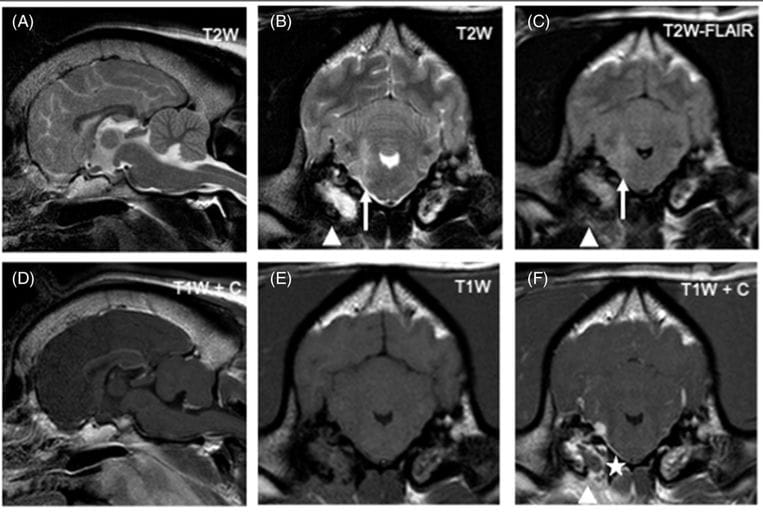

Magnetic resonance images of the head of a dog diagnosed with bacterial meningoencephalitis secondary to otogenic infection (dog 6). From left to right: Top row: sagittal T2W image (A), transverse T2W (B), transverse T2W-FLAIR (C); Bottom row: sagittal T1W postgadolinium (D), transverse T1W pregadolinium (E), transverse T1W postgadolinium administration (F). Transverse images are at the level of the tympanic bullae and, by convention, the right side of the dog is displayed on the left of the image. There is an ill-defined T2W and T2W-FLAIR hyperintensity (compared to normal gray matter) of the right rostral medulla oblongata extending dorsally into the middle cerebellar peduncle (white arrow). The adjacent meninges show contrast enhancement and a focal area of thickening (asterisk). There is bilateral T2W and T2W-FLAIR hyperintensity of the tympanic bullae contents (more pronounced and homogenous on the right), with bilateral contrast enhancement (again more pronounced on the right). Ventral to the right tympanic bulla there is ill-defined T2W and T2W-FLAIR hyperintensity of the soft tissues with marked contrast enhancement (arrowheads)